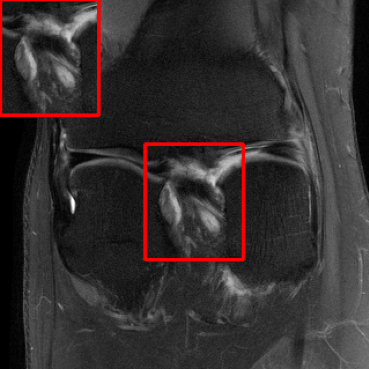

Results for the DIDN-based Reconstructor: To demonstrate adaptability to different network architectures, Table II compares reconstruction performance on the test set with the DIDN denoiser-based MoDL architecture. Average PSNR values with LONDN-MRI are compared to those with networks trained globally at different training set sizes. We ran only iteration of LONDN-MRI, where the reconstruction with a pre-trained (global) network was used to find neighbors. PSNR values for the oracle LONDN-MRI reconstructor are also shown. The overall performances with the DIDN-based architectures are better than with the UNet-based unrolled networks. The PSNRs for LONDN-MRI are consistently and similarly better than for the globally trained network across the different training set sizes considered, indicating potential for LONDN-MRI in improving state-of-the-art models. Fig. 6 visually compares reconstructions and reconstruction errors (in zoomed in region) for different methods. We can see that the LONDN reconstructors capture the original image features more sharply and accurately than the globally learned reconstruction.

| Ground Truth | Global | LONDN-MRI | Oracle |

| (1 iteration) | |||

![]() |

| PSNR = dB | PSNR = 34.15 dB | PSNR = 34.46 dB | PSNR = 34.54 dB |